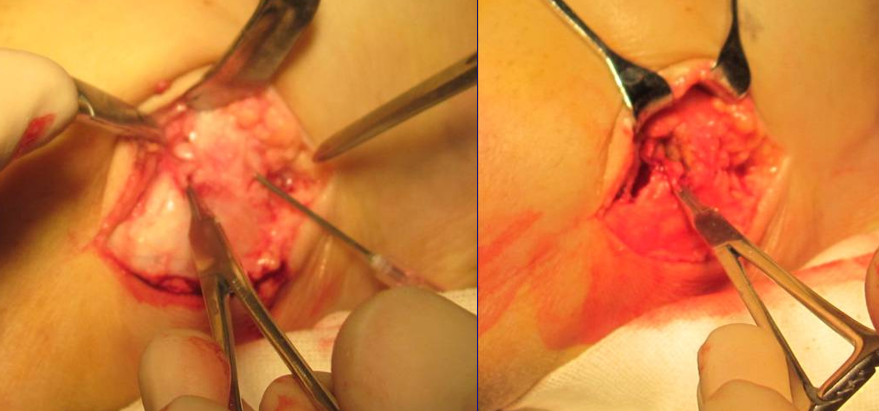

关节镜辅助下踝关节融合术

孔德春 男性 52岁

术后

植入异体骨条

关节清理后不植骨